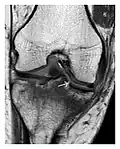

High-energy trauma fractures

Occult osseous injuries may result from a direct blow to the bone by compressive forces of adjacent bones against one another or by traction forces during an avulsion injury. Lesions in the tibial plateau, hip, ankle, and wrist are often missed. In a tibial plateau fracture, any disruption of the posterior and anterior cortical rims of the plateau should be sought. Impaction of subchondral bone will appear as an increased sclerosis of the subchondral bone (Figure 1). In the hip, posterior acetabular fractures also present subtle radiographic findings. The acetabular lines should then be carefully examined keeping in mind that the posterior rim, which is harder to see on X-rays, is more frequently fractured than the anterior rim (Figure 2). In the wrist, detection of carpal bone fractures is often challenging, with up to 18% of scaphoid fractures radiographically occult. Carpal fractures, especially the scaphoid, are associated with the risk of avascular necrosis. In apparently normal wrist radiographs from symptomatic patients, if there is history of a fall on an outstretched hand with pain in the anatomic snuffbox, suggesting scaphoid injury, the initial examination with posteroanterior, lateral, and pronation oblique views must be complemented by other specific views such as supination oblique and the "scaphoid" view A careful examination of cortices for evidence of discontinuity or offset and cancellous bone for lucency is necessary (Figure 3).[1]

Figure 1: A 56-year-old woman presenting with left knee pain after a fall. (a) Initial anteroposterior radiograph was considered normal, however, subtle cortical disruption of the anterior rim of the medial tibial plateau, medial to the tibial spine, is noted (arrow). (b) Coronal T1-weighted MRI confirms the cortical disruption (arrow) and shows extensive fracture through the proximal tibia. (c) Coronal proton density-weighted image with fat saturation shows extensive edema in the subchondral bone. Note also hypersignal adjacent to the medial collateral ligament corresponding to a grade I sprain (arrowheads).[1]